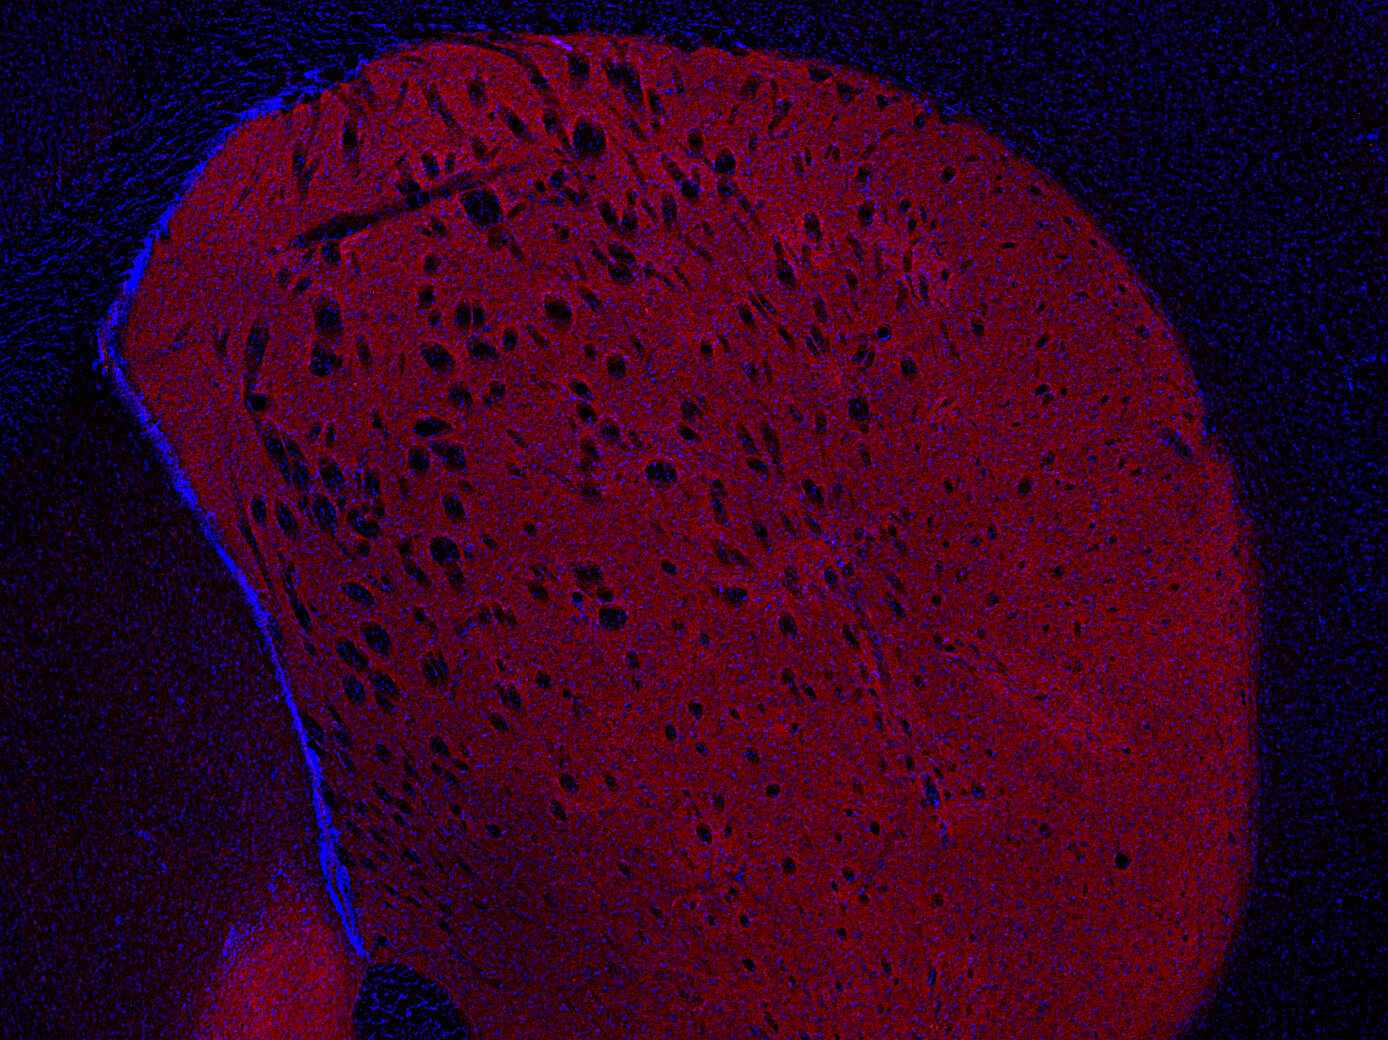

DOPA decarboxylase antibody - 369 004

IHC: 1 : 500 gallery

Immunohistochemistry (IHC) on 4% PFA perfusion fixed tissue with 24h PFA post fixation. Immunoreactivity is usually revealed by fluorescence or a chromogenic substrate. Some antibodies require special fixation methods or antigen retrieval steps. For details, please refer to the ”Remarks” section.

Specificity DOPA decarboxylase

DOPA decarboxylase, also referred to as aromatic L-amino acid decarboxylase, AADC or DDC, is the second enzyme in the biosynthesis of dopamine and serotonin. In addition, it is responsible for the synthesis of the trace amines phenylethylamine, p-tyramine, and tryptamine, which are considered to act as neuromodulators.

DDC is expressed in the central nervous system, but has also been detected in several tissues such as liver, kidney, small intestine, adrenal gland and blood vessels.